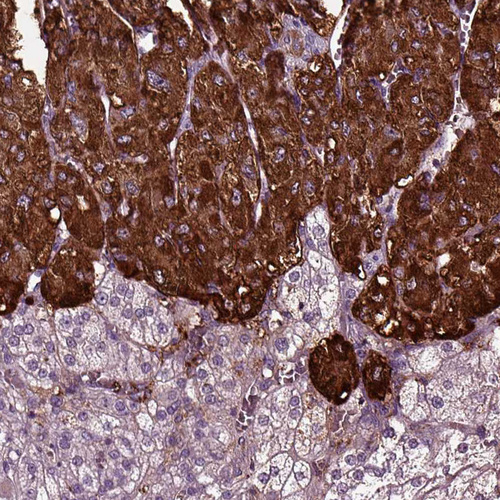

Immunohistochemistry analysis in human adrenal gland and liver tissues using HPA008759 antibody. Corresponding CHGB RNA-seq data are presented for the same tissues.